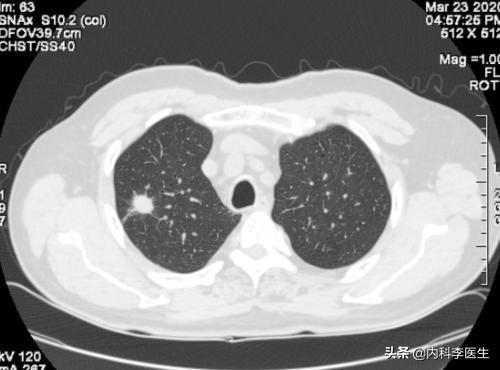

Les examens médicaux étant de plus en plus fréquents, les nodules pulmonaires sont de plus en plus souvent détectés. Les nodules pulmonaires sont un terme d'imagerie, et la définition d'imagerie d'un nodule pulmonaire est une petite lésion bien définie qui est complètement entourée par le parenchyme pulmonaire (Diamètre ≤30mm). La morphologie des nodules est classée comme solide ou sub-solide ; les nodules sub-solides sont eux-mêmes classés en nodules de verre dépoli et en nodules partiellement solides. Les lésions de plus de 30 mm de diamètre sont des masses plutôt que des nodules et ont une probabilité plus élevée d'être malignes.

La définition actuellement acceptée d'un nodule pulmonaire est une ombre pulmonaire focale, arrondie, hyperdense, solide ou subsolide, d'un diamètre ≤3 cm. Ces dernières années, avec l'augmentation de la population examinée par tomodensitométrie à faible dose, la proportion de nodules pulmonaires multiples détectés en plus des nodules pulmonaires isolés a considérablement augmenté. Les nodules pulmonaires multiples se présentent souvent sous la forme d'un nodule pulmonaire unique accompagné d'un ou plusieurs petits nodules. Les nodules pulmonaires multiples sont définis comme 2 lésions ou plus. Les patients présentant des nodules pulmonaires multiples peuvent avoir plusieurs sources de cancer du poumon précoce ou de lésions précancéreuses confirmées chirurgicalement et nécessitant une attention clinique particulière.

Qualitatif : Les nodules pulmonaires sont une anomalie impossible ou difficile à détecter par le patient ou les membres de sa famille. Il s'agit souvent d'une anomalie physique qui n'est détectée que lors d'une visite à l'hôpital pour des contrôles tels que des examens médicaux, et en utilisant des instruments tels que la tomodensitométrie, les rayons X et l'imagerie par résonance magnétique (IRM) des poumons.

En fonction de l'uniformité de la densité des nodules, on peut les classer en nodules substantiels, en nodules de verre dépoli purs et en nodules de verre dépoli mixtes.